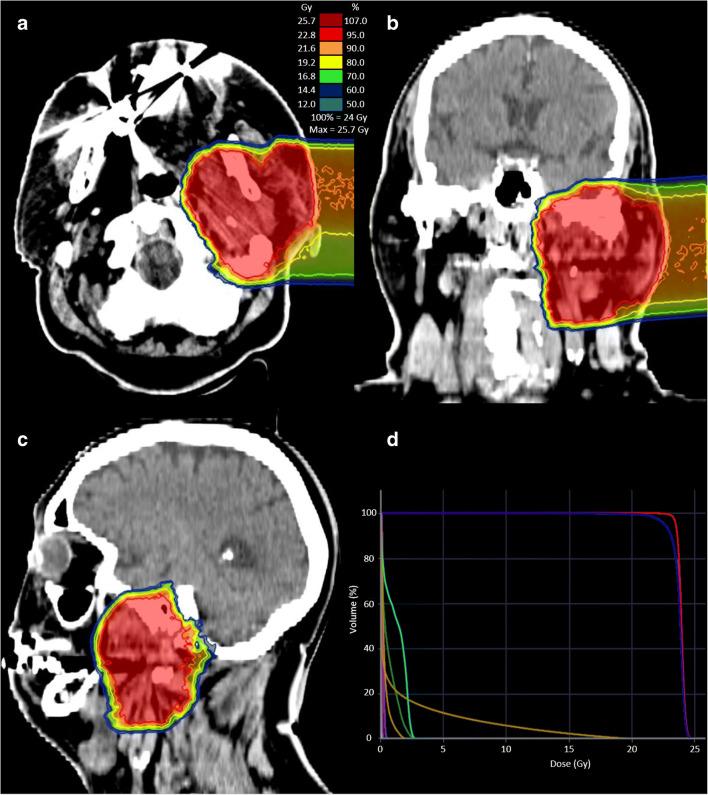

FAPI PET-CT was performed without complications prior to radiotherapy in addition to contrast enhanced CT (CE-CT) and MRI on 14 patients with HNC. First, for tissue biodistribution analysis, volumes of interest were defined to quantify SUV and SUV in tumour and healthy parenchyma. Secondly, using four thresholds of three-, five-, seven- and tenfold increase of FAPI enhancement in the tumour as compared with normal tissue, four different gross tumour volumes (FAPI-GTV) were created automatically. These were compared with GTVs created conventionally with CE-CT and MRI (CT-GTV).

The biodistribution analysis revealed high FAPI avidity within tumorous lesions (e.g. primary tumours, SUV 14.62 ± 4.44; SUV 7.41 ± 2.39). In contrast, low background uptake was measured in healthy tissues of the head and neck region (e.g. salivary glands: SUV 1.76 ± 0.31; SUV 1.23 ± 0.28). Considering radiation planning, CT-GTV was of 27.3 ml, whereas contouring with FAPI resulted in significantly different GTVs of 67.7 ml (FAPI × 3, p = 0.0134), 22.1 ml (FAPI × 5, p = 0.0419), 7.6 ml (FAPI × 7, p = 0.0001) and 2.3 ml (FAPI × 10, p = 0.0001). Taking these significant disparities between the GTVs into consideration, we merged FAPI-GTVs with CT-GTVs. This resulted in median volumes, that were, as compared to CT-GTVs, significantly larger with FAPI × 3 (54.7 ml, + 200.5% relative increase, p = 0.0005) and FAPI × 5 (15.0 ml, + 54.9%, p = 0.0122). Furthermore, FAPI-GTVs were not covered by CE-CT-based planning target volumes (CT-PTVs) in several cases.